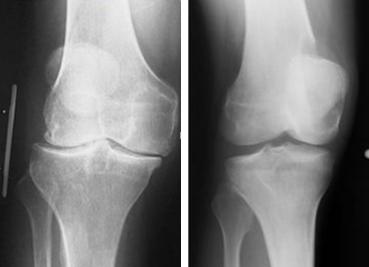

(图:唐先生膝关节肿胀明显,不能正常伸直弯曲,活动受限)

来院后,我院医生杜爱华主任在经过一番了解后,决定先对其进行检查了解病情的原因。检查后发现:抗O是84.4,血沉110/h,加上唐先生的膝关节肿胀明显,不能正常伸直弯曲,活动受限,关节遭受到严重的破坏,关节面边缘模糊不清,诊断为风湿性关节炎。

(图:从x光片上可以明显看出治疗前后的不同,唐先生已恢复正常)